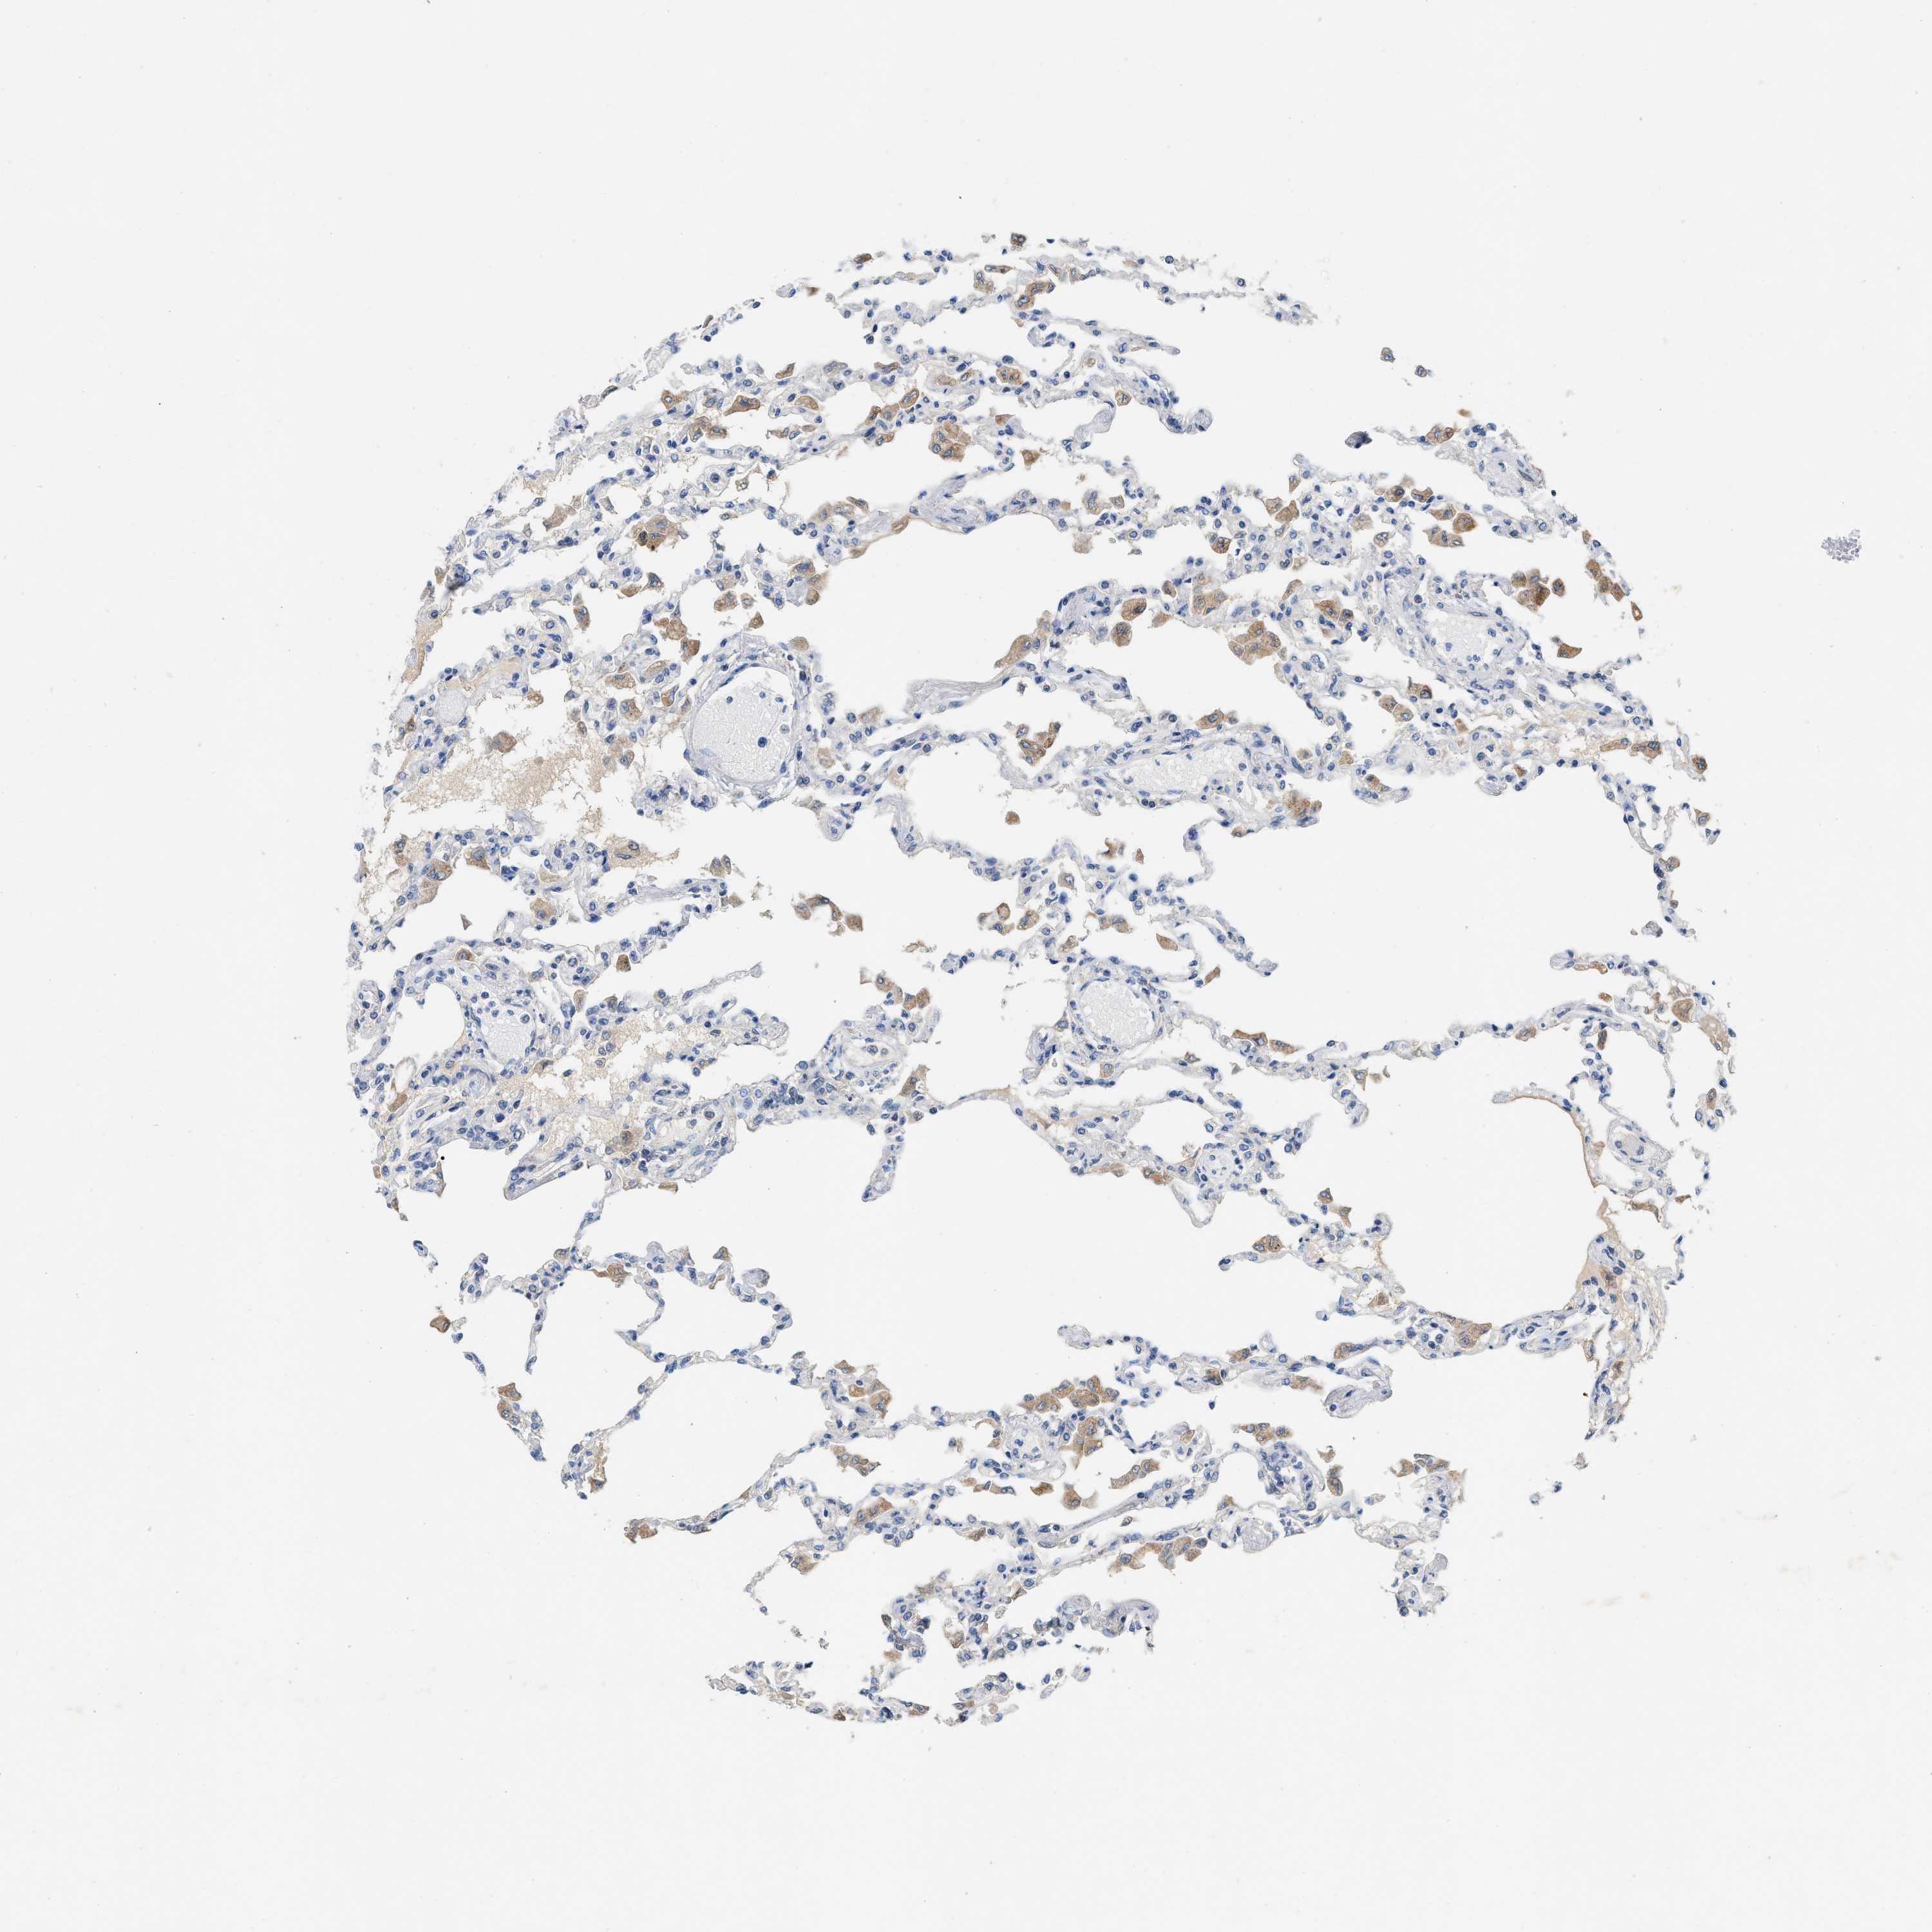

LUNG - Antibody stainingi

Antibody staining in the annotated cell types in the current human tissue is reported as not detected, low, medium, or high, based on conventional immunohistochemistry profiling in selected tissues. This score is based on the combination of the staining intensity and fraction of stained cells.

Each image is clickable and will lead to virtual microscopy that enables deeper exploration of all samples and also displays staining intensity scores, fraction scores and subcellular localization as well as patient and tissue information for each sample.

Antibody HPA020375

Alveolar cells Not detected

Macrophages Medium